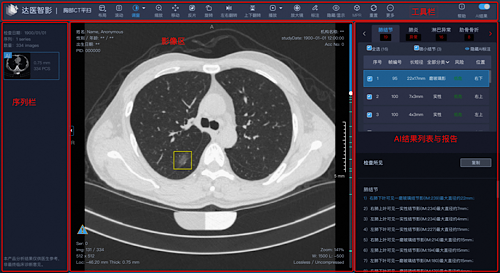

据悉,项目依托阿里巴巴达摩院医疗AI实验室自研的智能读片产品“达医智影”。通过常规胸部、腹部CT平扫,以突破性的“平扫CT+AI”方式帮助诊疗,胰腺癌、肝癌、食管癌、胃癌、结肠癌等占据新发癌量38.1%的病灶发现,辅助医生对骨质疏松、脂肪肝及肺结节等总计13个病种进行疾病筛查、诊断、治疗和随访全流程,提高临床诊断准确率和效率。

达医智影可以辅助医生进行疾病筛查、诊断

第一,效率极大提升:从人工5-15分钟判断单病种,提升到2-3分钟可判断多个病种。第二,准确性极大提升:对各病种诊断的敏感性和特异性数据,均满足相应病种的准确性要求。第三,多癌综合检出:从单病种检查到一次胸部CT检查多个病种的提升。第四,拓宽诊疗能力边界:已可实现对胰腺癌和食管癌的有效早筛。第五,数智化程度高:数据可视化,实现智能筛查、辅助诊断、量化分析。